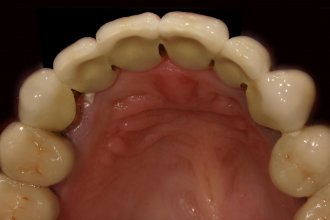

Metallkeramikbrückenglieder im Frontzahnbereich

Wenn mehrere Zähne im Frontzahnbereich fehlen, kann man die Lücke durch eine Brücke schließen. Meistens ist dann auch schon der Kieferkamm zurückgeschwunden. Dadurch wirken die Brückenglieder länger. Auch die Zahnfleischpapille fehlt. Hier haben wir sie mit rosa Keramik nachgebildet, um „dunkle Löcher“ zwischen den Zähnen zu vermeiden und die Zähne nicht unnatürlich breit und lang erscheinen zu lassen.